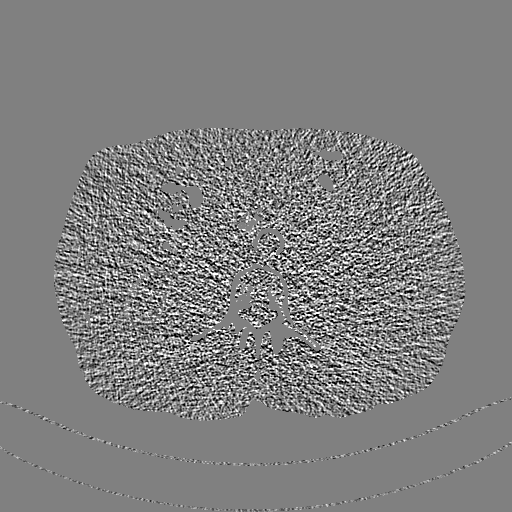

Refer to caption

(a) Original LDCT

(b) Predicted LDCT

(c) Original Noise

(d) Predicted Noise

Figure 5: Performance of invertible network in reverse mapping. The display window for CT images is [160160-160, 240] HU, and for noise pattern [5050-50, 50] HU

This section systemically investigates the efficacy of every module proposed in this study. We considered three different networks; first, baseline model(M1), where the inverting block is replaced with dense block, and trained using minimizing mean square distance between two noisy observations(i.e. fsubscript𝑓\mathcal{L}_{f}). Next, two independent baseline model(one for forward mapping, one for reverse mapping) is jointly trained using a linear combination fsubscript𝑓\mathcal{L}_{f}, and rsubscript𝑟\mathcal{L}_{r}, similar to cycle consistent network paradigm. The forward mapping network is used for testing. We refer this model as M2. In both M1, and M2, we increased the depth of the network to make the representation power of these networks comparable with inverting network. Finally, the proposed method, referred as M3. Table 2 depicts the objective evaluation of the three networks using the D1 dataset. Both M2 and M3 use reverse mapping to regularize the network; the influence of the same in the denoising performance is evident from Table 2. Adding cycle consistency loss has improved the performance of the same baseline model significantly. The inverting network performed considerably better than the network M2. It improves PSNR by 0.23dB. As discussed in the above section, in case cycle consistency loss, an additional network is trained, but that does not always guarantee invertibility, whereas inverting network architecture inherently possesses reversibility, which acts as a strong regularizer. In Figure 3 we have shown denoising performance of different networks visually. To demonstrate the requirement of regularization, we first extract the boundary line of the various organ from the NDCT image and superimpose the boundary line on the output of different networks. As shown in Figure 3, many pixels around the boundary line of M1 network output are missing. Using the reverse mapping, the issue of the end-organ missing pixel is successfully overcome in M2 and M3. The granular pattern is also less present in the M3 than M2. The zoomed version of a ROI taken from the images of Figure 3 is given in Figure 4 for better perception. In Figure 5 we give an example of the performance of the invertible network in reverse mapping. Here, the predicted LDCT image is produced by using the predicted clean image of the forward mapping as the input for reverse mapping. As shown, the predicted noisy pattern is similar to the original noise pattern. The same streaking artifacts are present in both the noise pattern; also, the noise variance is different in the various spatial region depending on the signal intensity of the original CT image. It validates that the loss of information in reverse mapping is minimal. Due to the invertible network’s structural advantage, the network also preserves every information present in the input image in the forward mapping.